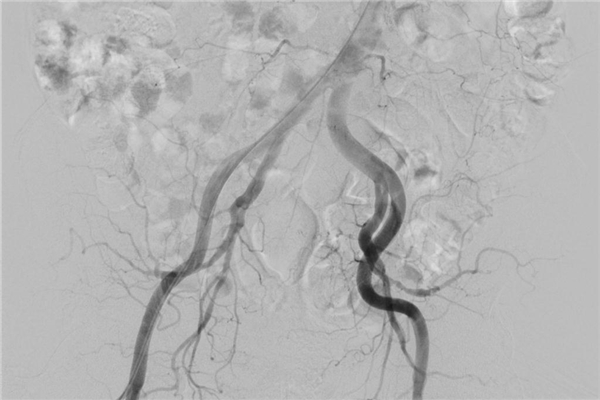

后经左侧前列腺动脉插入微导管造影,可见迂曲的动脉(如下图),这给手术增加了一定难度。